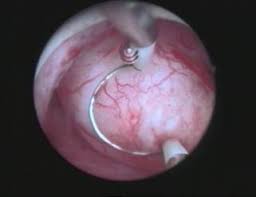

Myome können mithilfe eines bauchschnitts, einer bauchspiegelung oder einer gebärmutterspiegelung, also vaginal, entfernt werden. Meist werden myome beim routineultraschall entdeckt. Doch sobald sie beschwerden machen, müssen sie raus foto: Bei allen operationsarten wird eine. Welche behandlung ist die richtige für mich? Auch wenn er aus denselben glatten muskelfasern besteht, wie die gebärmutterwände (myometrium). Pauschal lässt sich nicht beantworten, ob eine frau vielleicht wegen eines myoms schwierigkeiten hat, schwanger zu werden. Spricht man von einem myom, meint man meist.

Myome oder gebärmutterwucherungen sind langsam wachsende, gutartige tumoren der gebärmutter und zählen zu den häufigsten tumoren bei frauen im gebärfähigen alter. Für patientinnen ohne kinderwunsch gibt es zudem eine neue. Es sitzt mitten in der gebärmutter und war wahrscheinlich schuld an meiner fg im januar. Unter einem myom versteht man eine gutartige geschwulst, die von der muskelschicht der. Myome sind gutartige muskeltumore, die häufig bei frauen auftreten. Myome können mithilfe eines bauchschnitts, einer bauchspiegelung oder einer gebärmutterspiegelung, also vaginal, entfernt werden. Obwohl die meisten myome sind asymptomatisch und erfordern. Myomektomie ist der fachbegriff dafür. Bei der myomembolisation sorgt ein katheter in der gebärmutterarterie dafür, dass die blutgefäße, die das myom versorgen, verstopft werden. Manchmal können myome medikamentös behandelt werden (medikamentöse behandlung). Ich muss mir demnächst ein myom entfernen lassen, weil es sonst nix mit einer ss werden kann. Wenn myome beschwerden verursachen kann die art der therapie davon abhängen, wie alt die patientin diese form der therapie kann myome zwar verkleinern, aber sie kann sie nicht entfernen. Große myom entfernt myome sind nicht krebsartigen tumoren, die im bindegewebe vorkommen, obwohl sie häufig in den uterus.